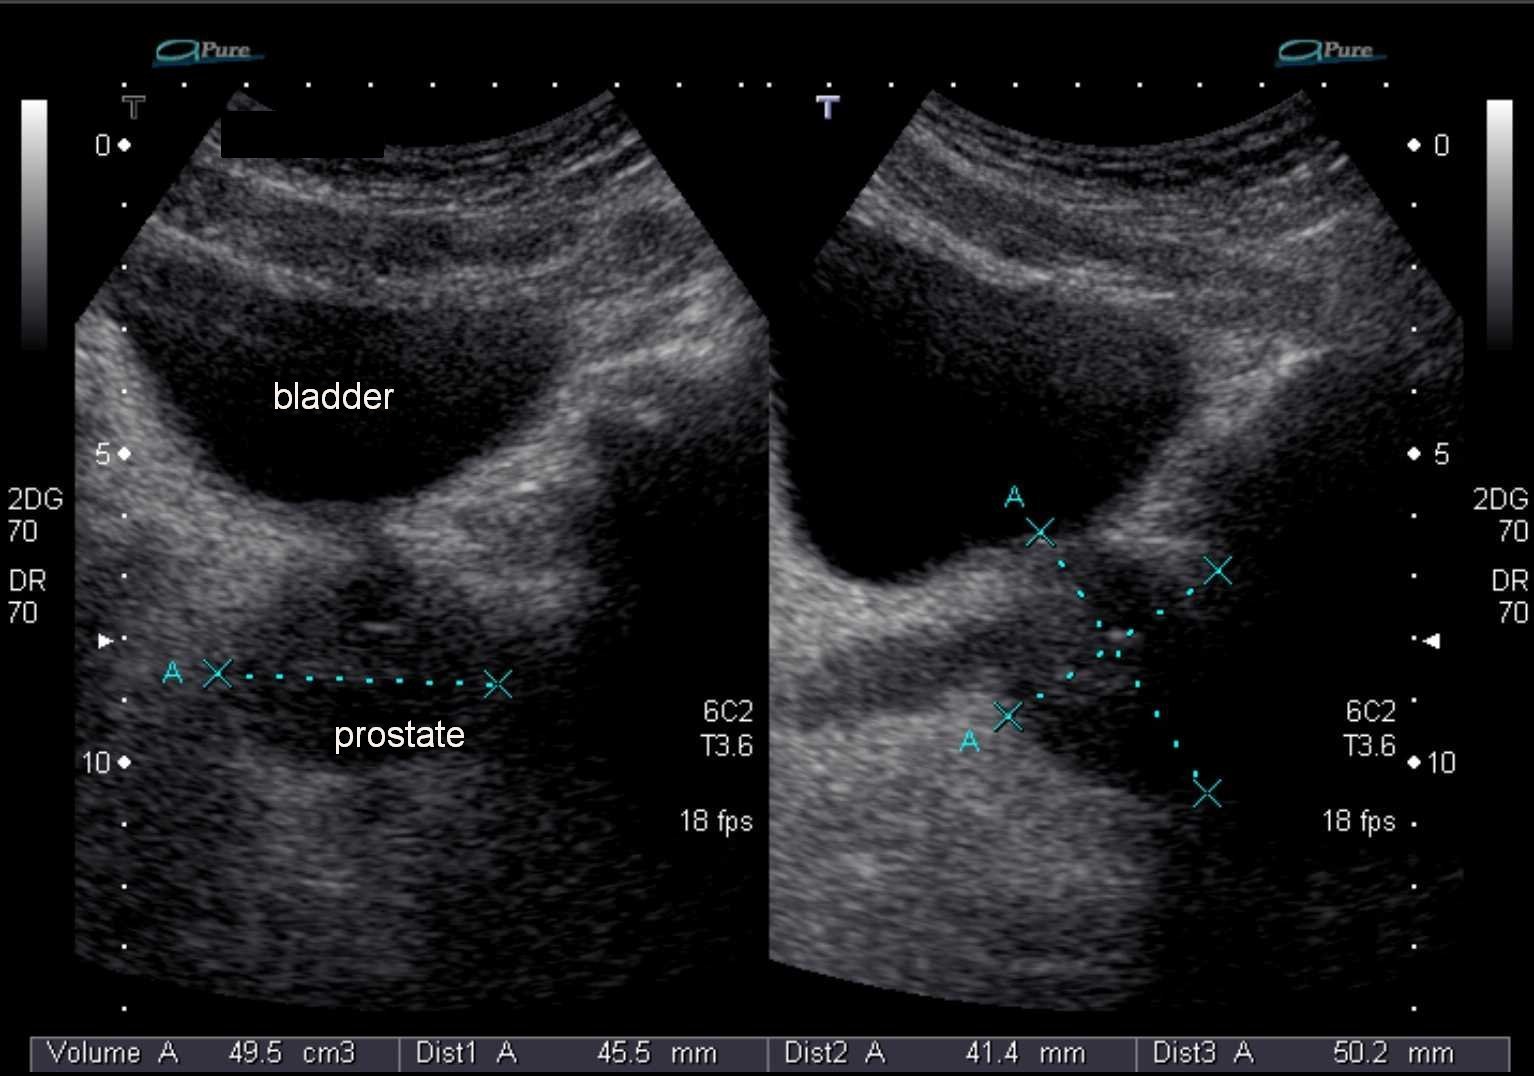

Что показывает ТРУЗИ

При трансректальном УЗ-обследовании оценивают следующие параметры (в скобках указаны варианты нормы):

- верхненижний размер (длина 24 – 40 мм);

- переднезадний размер (толщина 15 – 25 мм);

- поперечный размер (ширина 30 — 45 мм);

- суммарный объем предстательной железы (от 18,7 до 26, 8 см);

- эхогенность (средняя);

- симметричность;

- контуры (четкие ровные);

- форма (округлая/ треугольная);

- структуру центральной и периферической зоны (неоднородная мелкозернистая);

- объемные образования (в норме отсутствуют);

- парауретральный фиброз (отсутствует);

- структуру и размеры семенных пузырьков (в зависимости от акта семяизвержения и вовлеченности в воспалительный процесс, в норме структура однородная, если давно не было эякуляции – могут быть расширены);

- семявыносящие протоки (отсутствие кист);

- наличие срединной доли (утяжеляет прогноз при ДГПЖ);

- количество остаточной мочи (не больше 15 – 20 мл).

Объем предстательной железы может быть рассчитан по формуле и зависит от возраста мужчины, генетических особенностей, длительности воздержания, половой конституции и пр.

Формула для вычисления объема простаты представляет собой произведение 4 величин: толщины, длины, ширины и коэффициента 0,52.